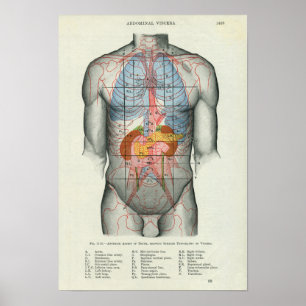

Viscera och buksmärtor Poster Fransk

Pris390,00 kr

Anatomi i mänskliga organ vykort

Pris23,00 kr

Anatomi i mänskliga organ poster

Pris229,00 kr

Anatomi i mänskliga organ canvastryck

Pris1 425,00 kr

Anatomi i mänskliga organ hälsningskort

Försäljningspris 49,00 kr. Ursprungligt pris 54,00 kr.